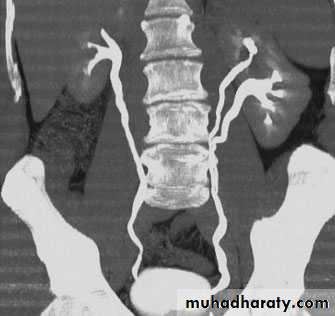

4. Horseshow kidney: fusion of the lower

pole, long axis parallel to the spine, mal-rotationof both kidneys so the pelvis of the kidneys

directed anterior or lateral . Obstruction and

infection are common . Its diagnosis is suggested

by US and confirmed by IVU or CT